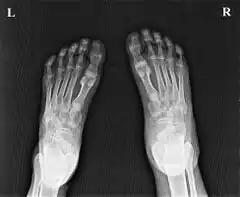

| Ainhum of the left foot of a Zulu patient in Ngwelezane Hospital, KZN, South Africa.(The little toe on the opposite foot had auto-amputated several years earlier.) | |

Soft tissue constriction on the medial aspect of the fifth toe is the most frequently presented radiological sign in the early stages. Distal swelling of the toe is considered to be a feature of the disease. In grade III lesions osteolysis is seen in the region of the proximal interphalangeal joint with a characteristic tapering effect. Dispersal of the head of the proximal phalanx is frequently seen. Finally, after autoamputation, the base of the proximal phalanx remains. Radiological examination allows early diagnosis and staging of ainhum. Early diagnosis is crucial to prevent amputation. Doppler shows decreased blood flow in posterior tibial artery.